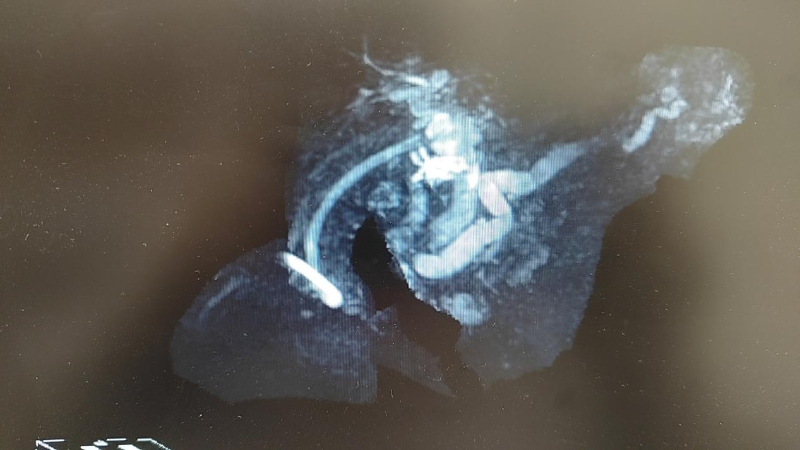

图片 2

(MRCP3D图像,提示肝内外胆管及主胰管扩张)